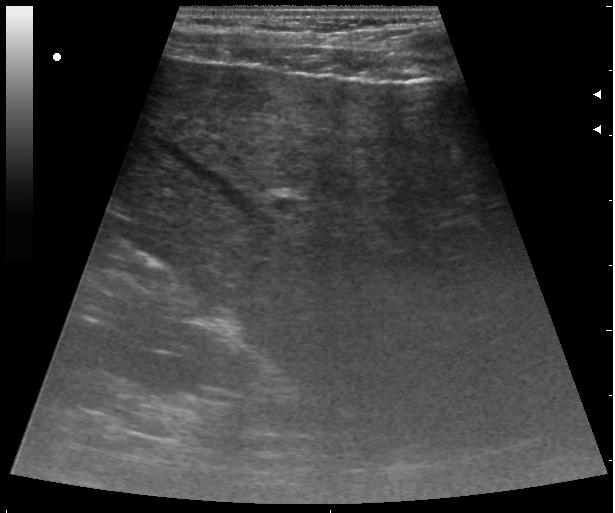

сегодня был селезёночный день.